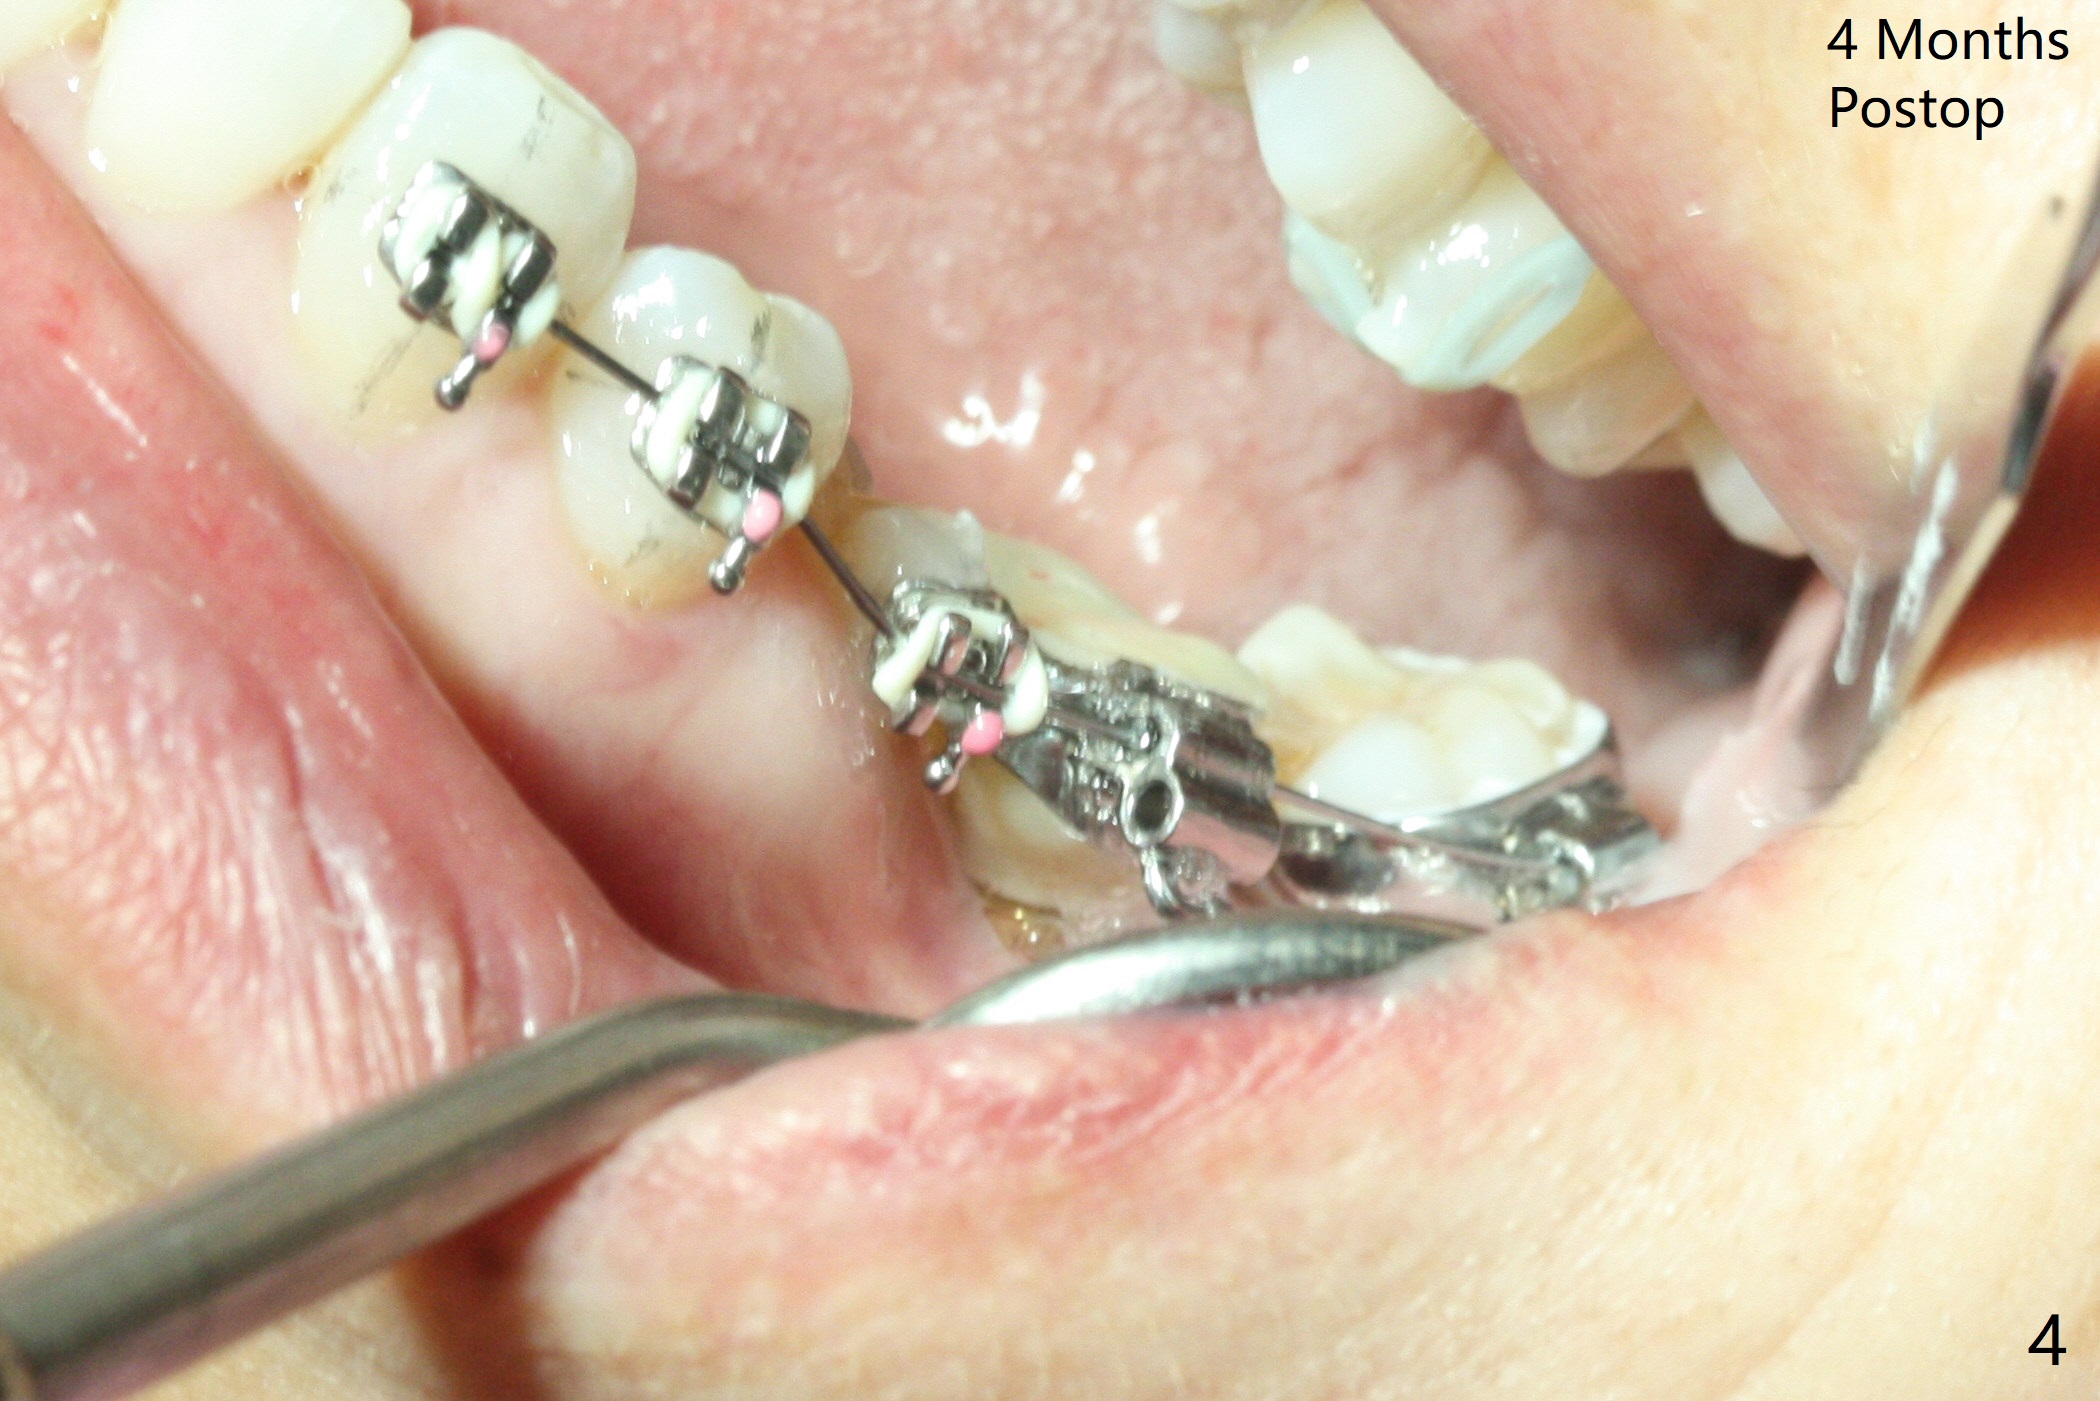

With 34 mg of Lidocaine and 17 mcg of Epinephrine (local infiltration), a 4.5x8.5 mm implant is placed with guide. The insertion torque is ~50 Ncm. It is placed in precise depth and in a short period of time (tolerable to the operators and patient, easier than mini-implant placement, Fig.1). There is no postop pain or paresthesia. The mesidistal position is within treatment plan (Fig.2). Miniimplants are placed to intrude #14 14 days prior. The teeth #16,17 and 32 are extracted 3 months postop. Minimal bone resorption at the crest is noted nearly 4 months postop (Fig.3). Bands and brackets are placed #18 upright 4 months postop (Fig.4 (14 niti wire)). The buccal and lingual view of the preop model shows that the supraerupted 1st molar (#14) has close relationship with the distal surface of the tooth #20 (Fig.5,6), accounting for the severe wear of the latter (Fig.8-11). The implant not only acts as an anchor to upright #18 in 4.5 months post banding (Fig.7 *), but also as an occlusal stop so that #18 has no interference to be moved. The stress on the implant results in radiating trabecular pattern (Fig.7,11 (9,11 months postop), as compared to before loading (Fig.1,3)). Restoring the distal contour of #20 with composite (Fig.12 C) makes it easy to close the space by adding porcelain the mesial surface of the implant crown. The crown/abutment is loose in China 7 months post cementation.